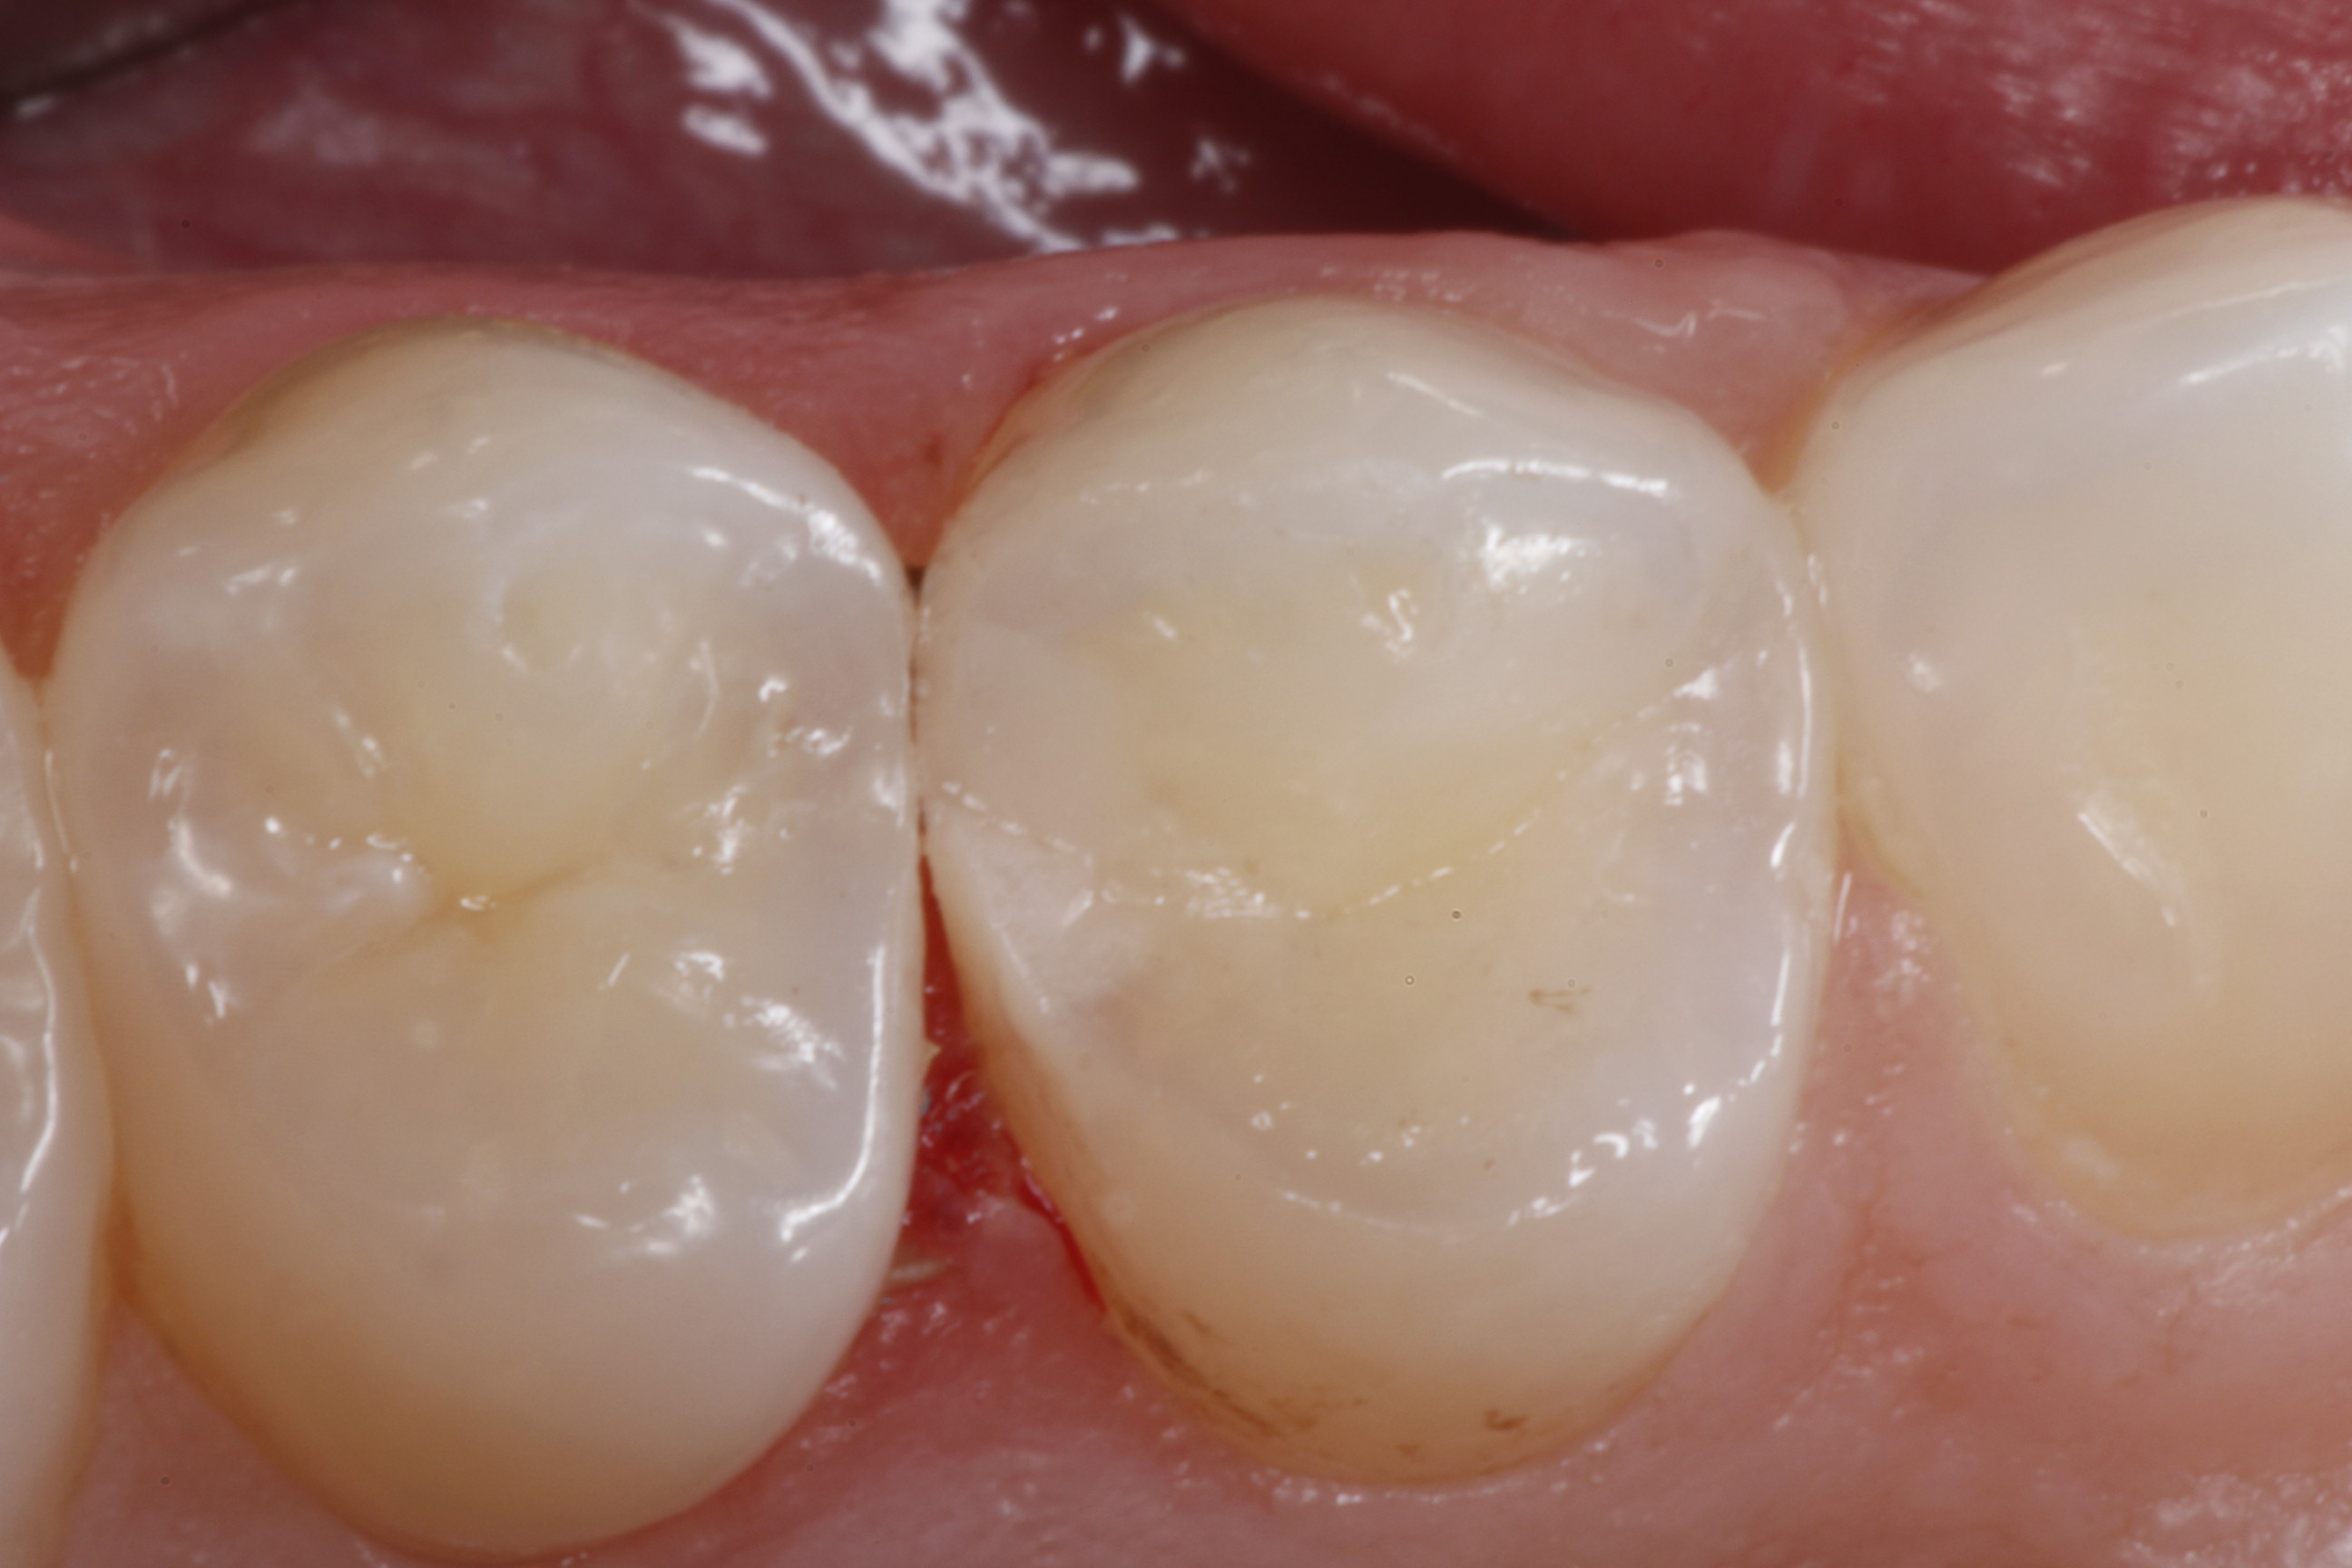

Fig 25. An occlusal view of the completed Giomer bulk-filled composite restorations on teeth Nos. 29 and 30.

Figure 25